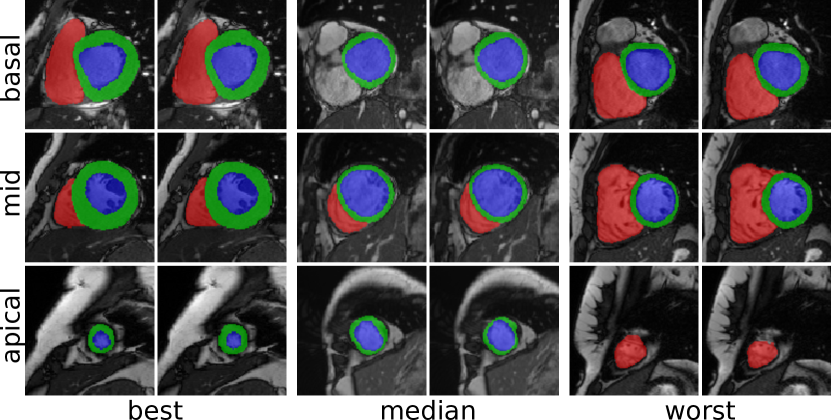

Clinical measures for the best performing method (the modified 2D U-Net) are shown in Table 3. A detailed description of the measures is provided by ACDC3. Figure 1 shows example segmentation results at three slice positions using the above method. Inference on a single volume took approximately 1.1 ssecond\mathrm{s} for the 2D networks and 2.2 ssecond\mathrm{s} for the 3D networks using a Nvidia Titan Xp GPU.

Refer to caption

Figure 1: Example segmentations at ED obtained using the 2D U-Net (mod.) for subjects with the highest, median, and lowest Dice coefficients on the Myocardium (left to right). Ground truth (left) and predicted segmentation (right) are shown for a basal, mid-ventricular and apical slice (top to bottom).